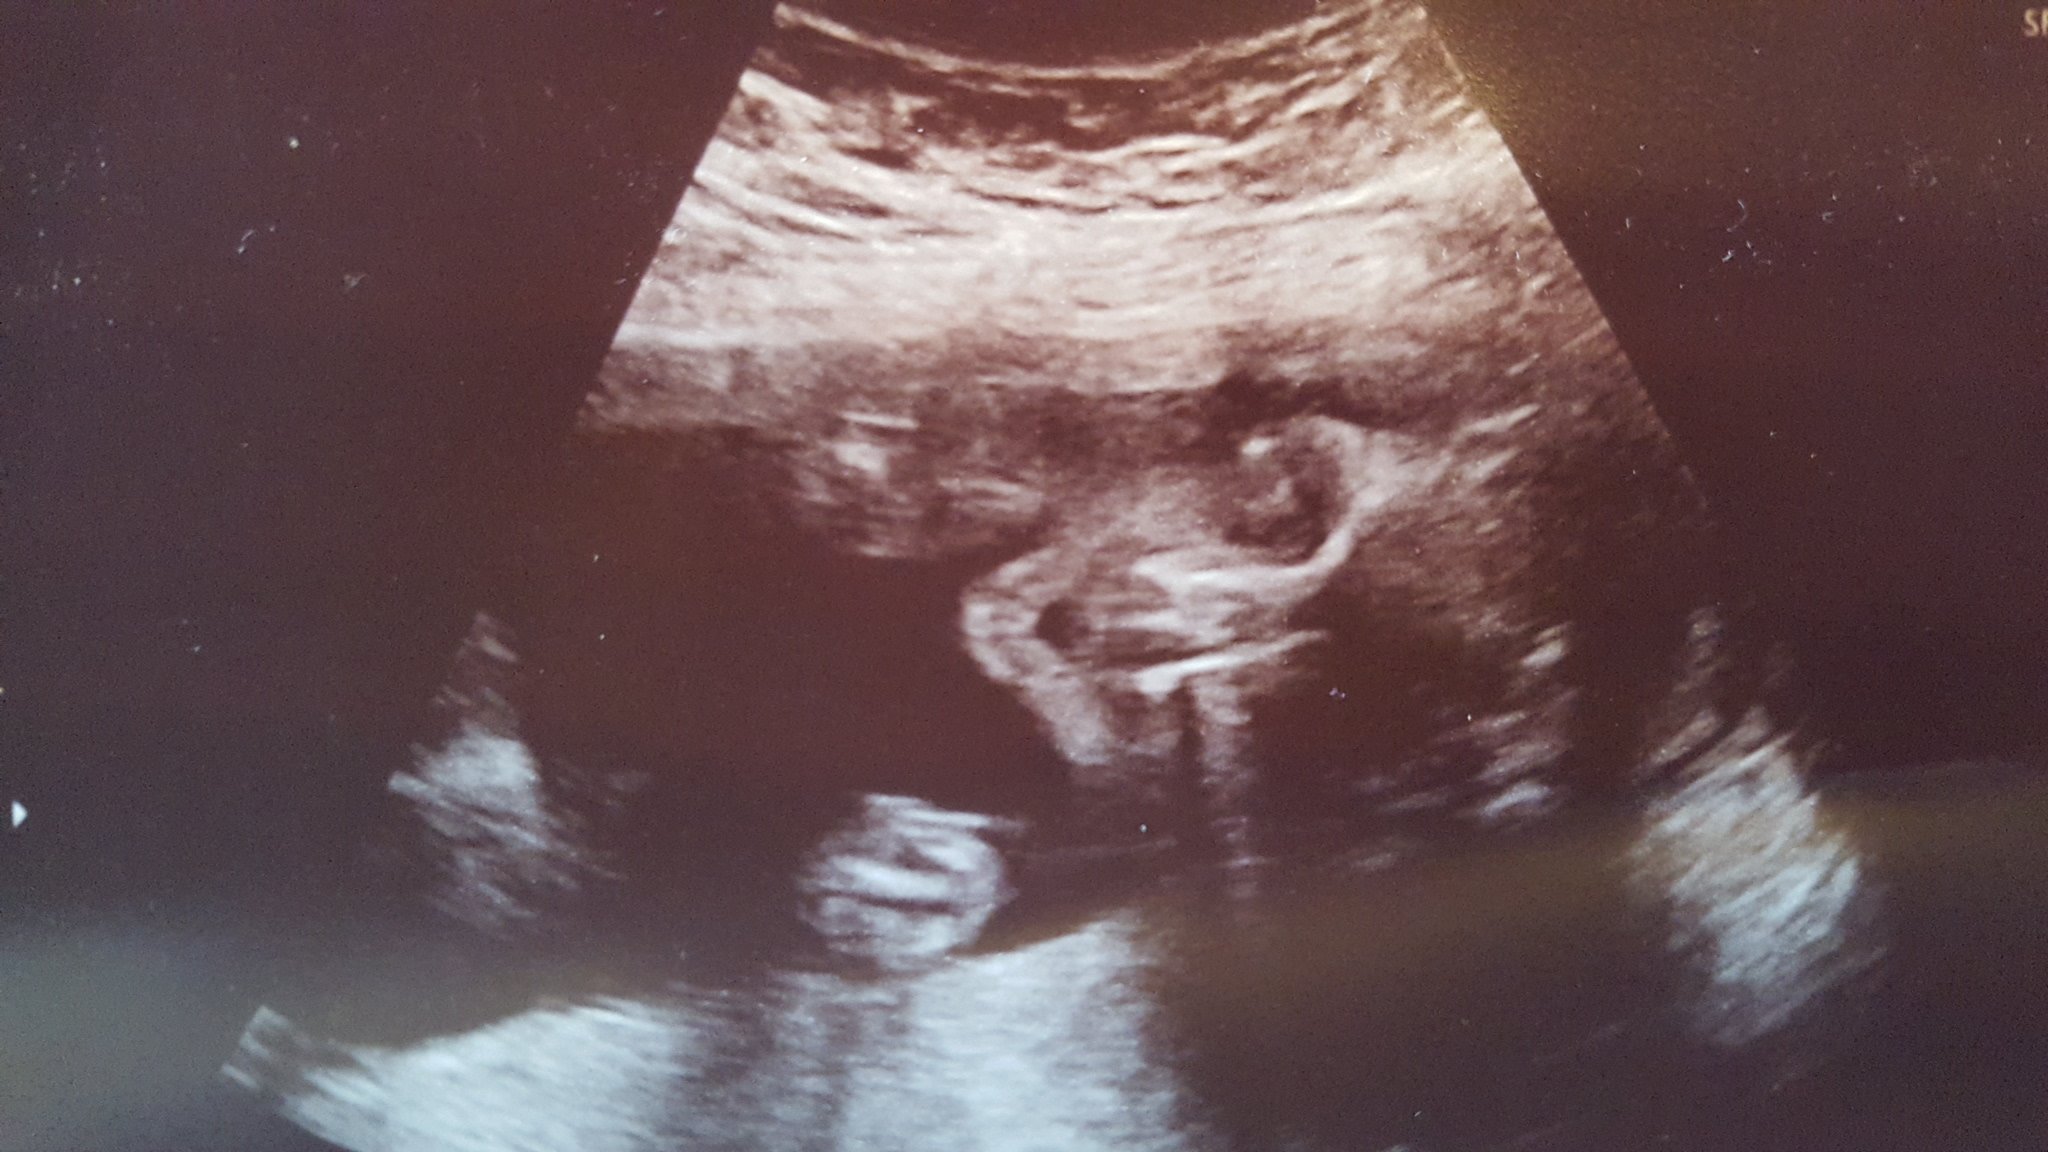

Had our scan today! She was curled in a ball with her hands together in front of her face and her feet crossed most of the time. (DD did the same thing for her scan) They were able to see almost everything but we are going back in 4 weeks to get a better look at anything they couldn't see. They confirmed girl and she weighed in at 11oz!